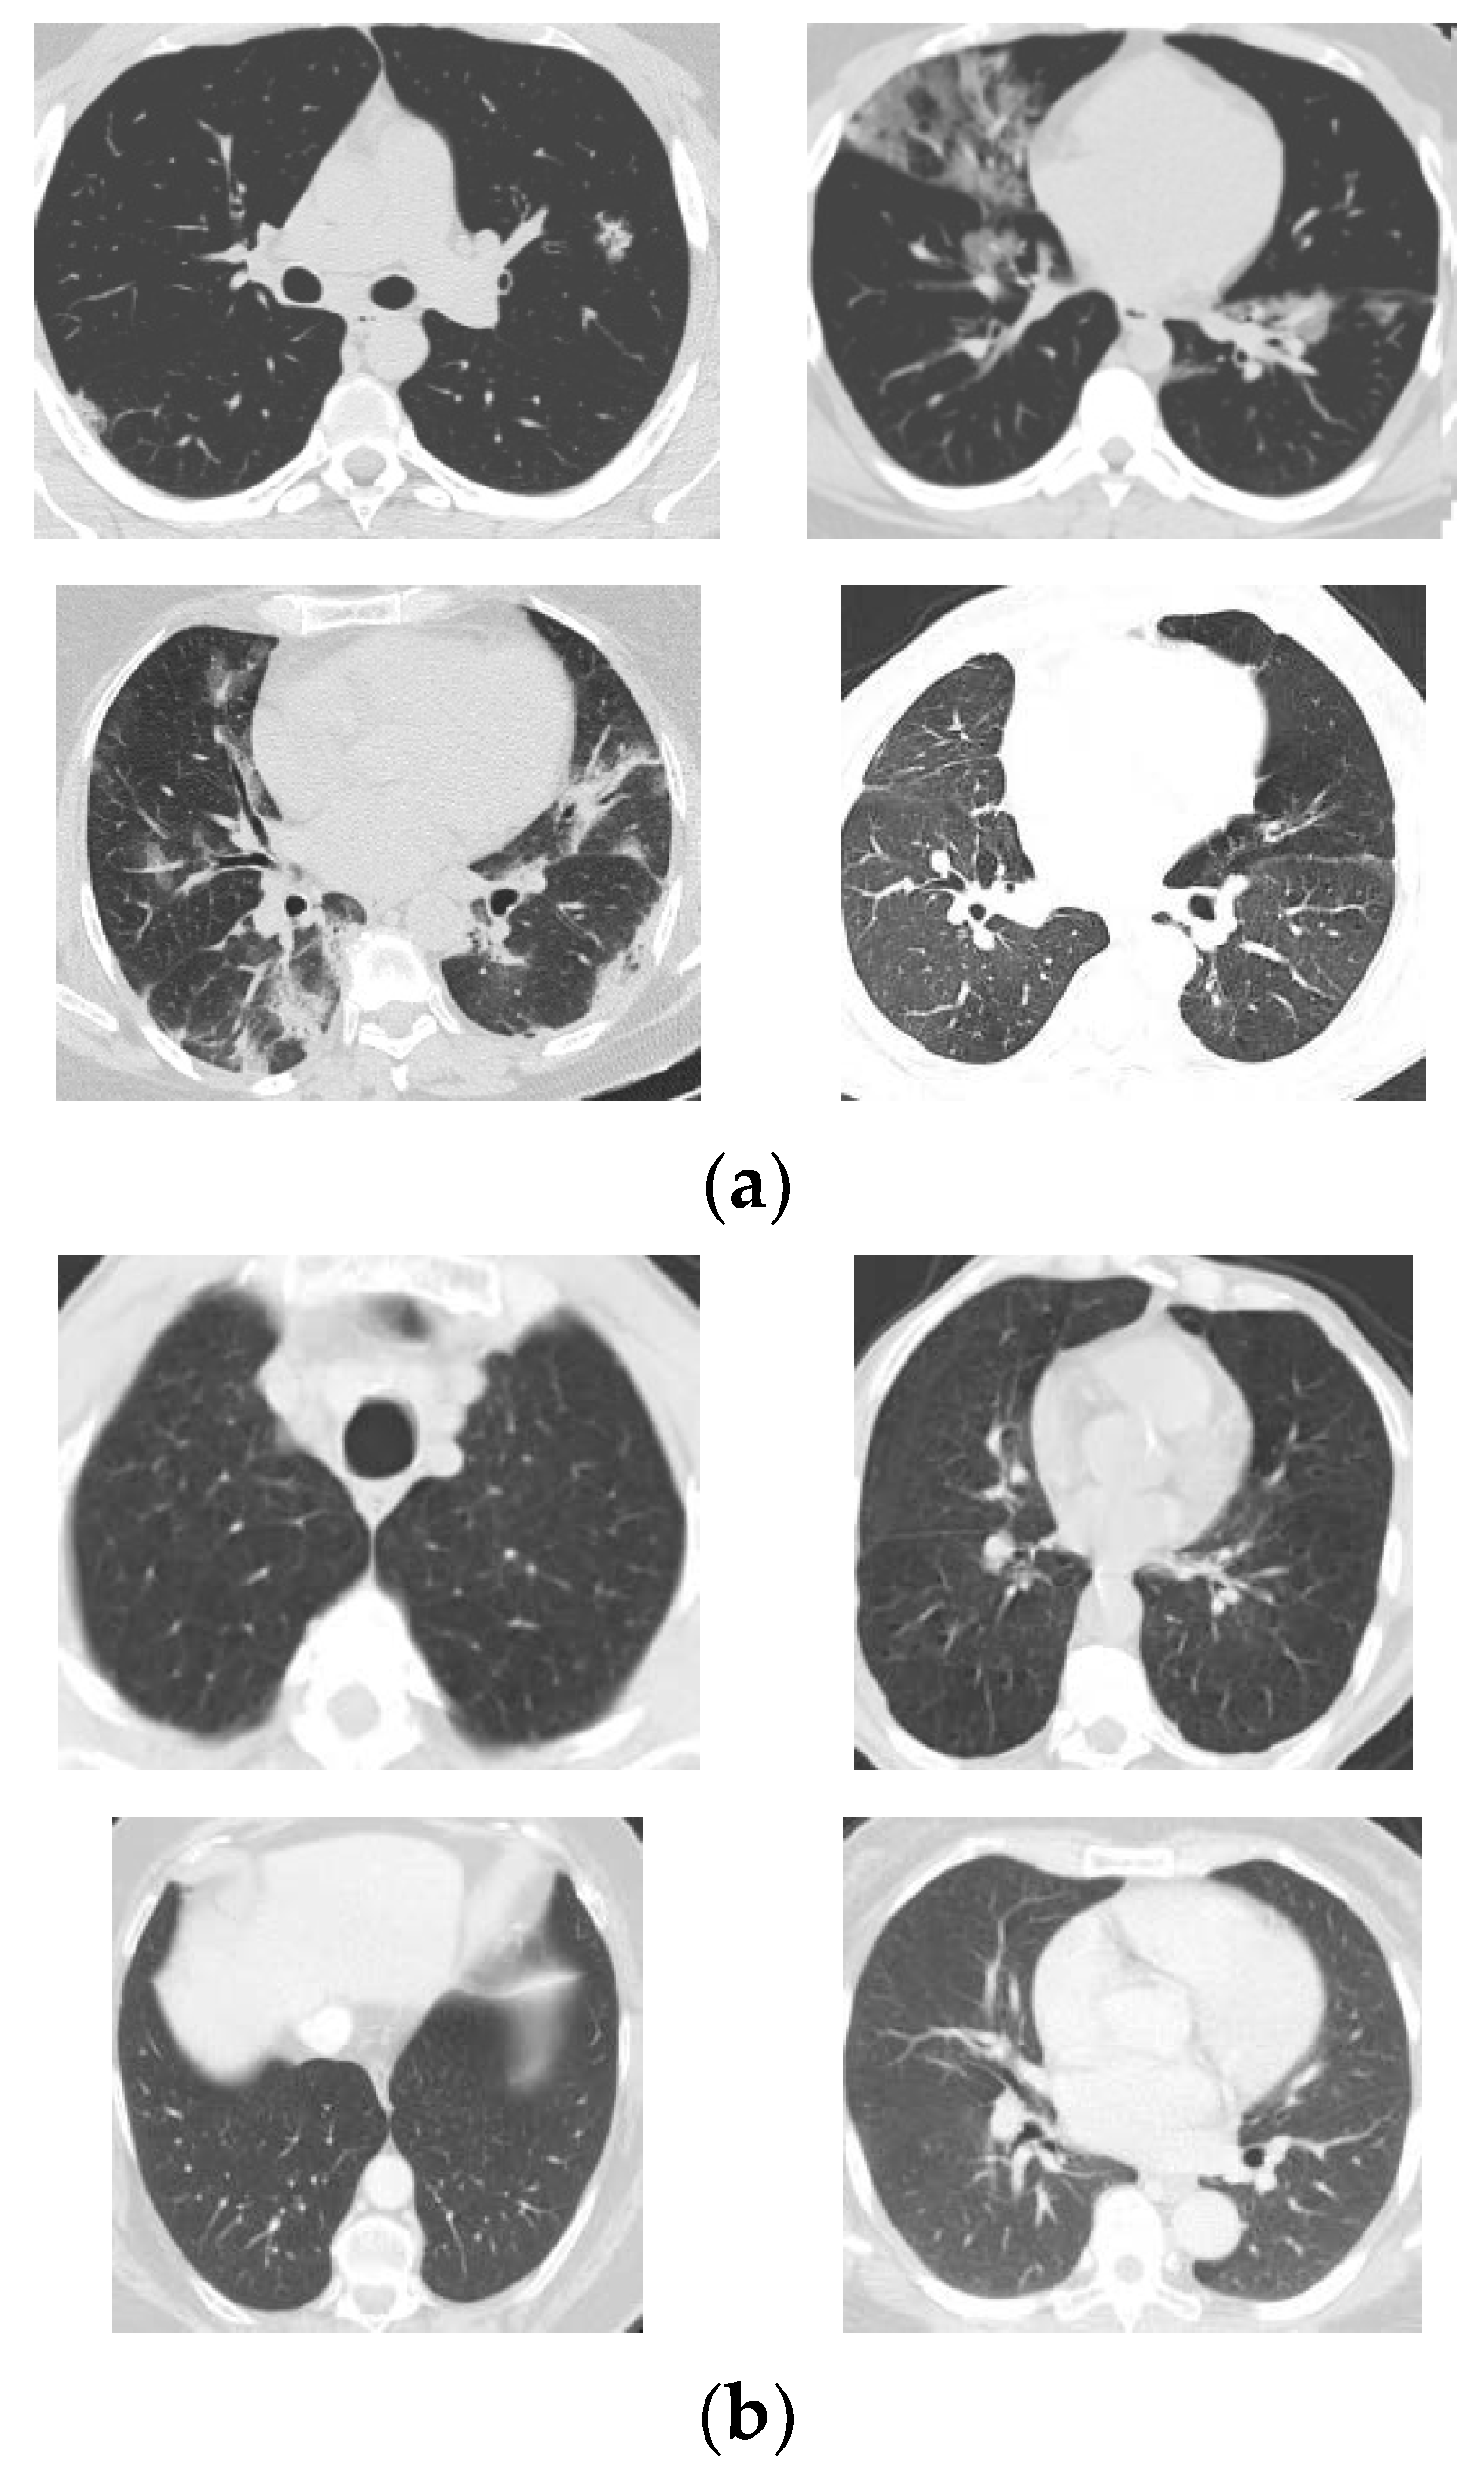

All the CT scans are from patients in Brazil. There are 1252 COVID-19 positive samples and 1230 non-COVID-19 ones in the public dataset. The non-COVID-19 samples mean that the patients are not affected with COVID-19 but other pulmonary diseases. The resolution of the CT scans varies from around 100 × 100 to around 500 × 500. Therefore, all the images need to be resized to the dimension of the input layer of the CGENet before training and testing. More details of the SARS-CoV-2 dataset are presented in the works of literature refs. [10,23]. Some random CT scans in the dataset are listed in Figure 1.

Figure 1. Random CT scans in the SARS-CoV-2 dataset ((a) COVID-19 samples, (b) Non-COVID-19 samples).